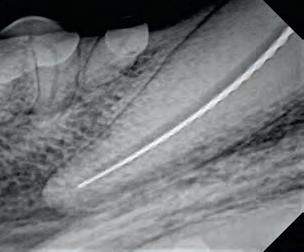

De dentale röntgenfoto van deze knipkies in de bovenkaak. Rondom de punten van de wortels zijn abcessen ontstaan, veroorzaakt door de bacteriën vanuit de geïnfecteerde kies. Het kaakbot is verdwenen door de infectie in het botweefsel. Op de röntgenfoto zijn deze abcessen zichtbaar als zwarte (botarme) cirkels/ovalen rondom de wortelpunten (lichtgeel omlijnd).